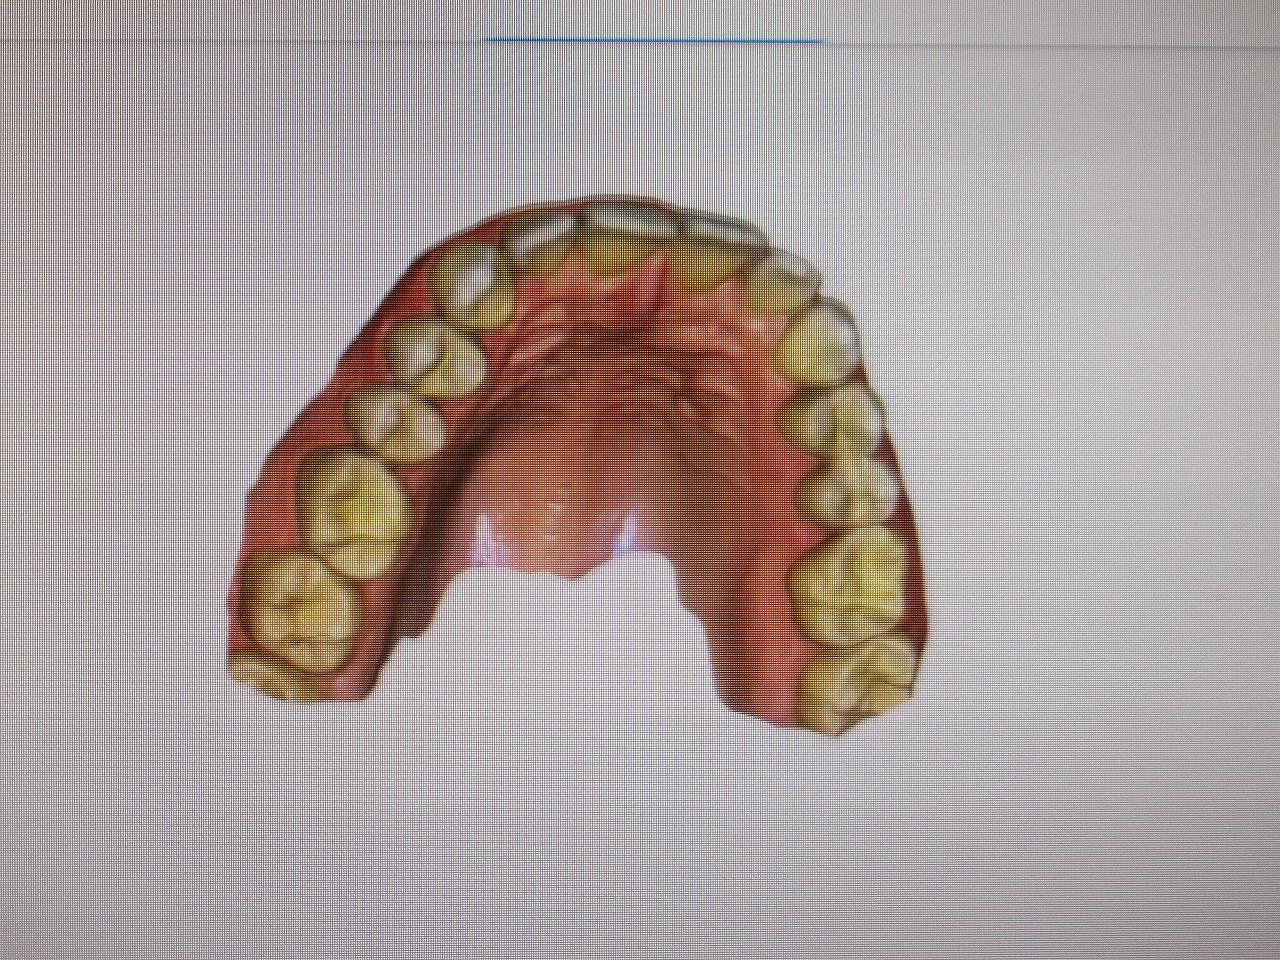

銀歯の術前 術後

プライムスキャンにてセラミックにて作成しています

制度が今までより上がっています